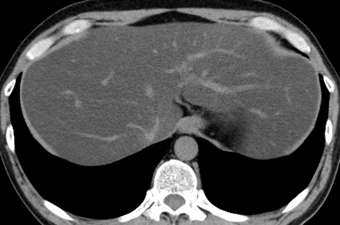

症状が食道での活動性出血を示している場合、医師は食道胃十二指腸鏡検査 (EGD)と呼ばれる検査を行うことがあります。

この処置中の不快感を防ぐために、鎮静剤と鎮痛剤を服用する必要があります。医師は、内視鏡と呼ばれる、カメラが取り付けられた小さな柔軟なチューブを食道から胃に挿入します。これは、医師が食道を観察し、裂傷の位置を特定するのに役立ちます。